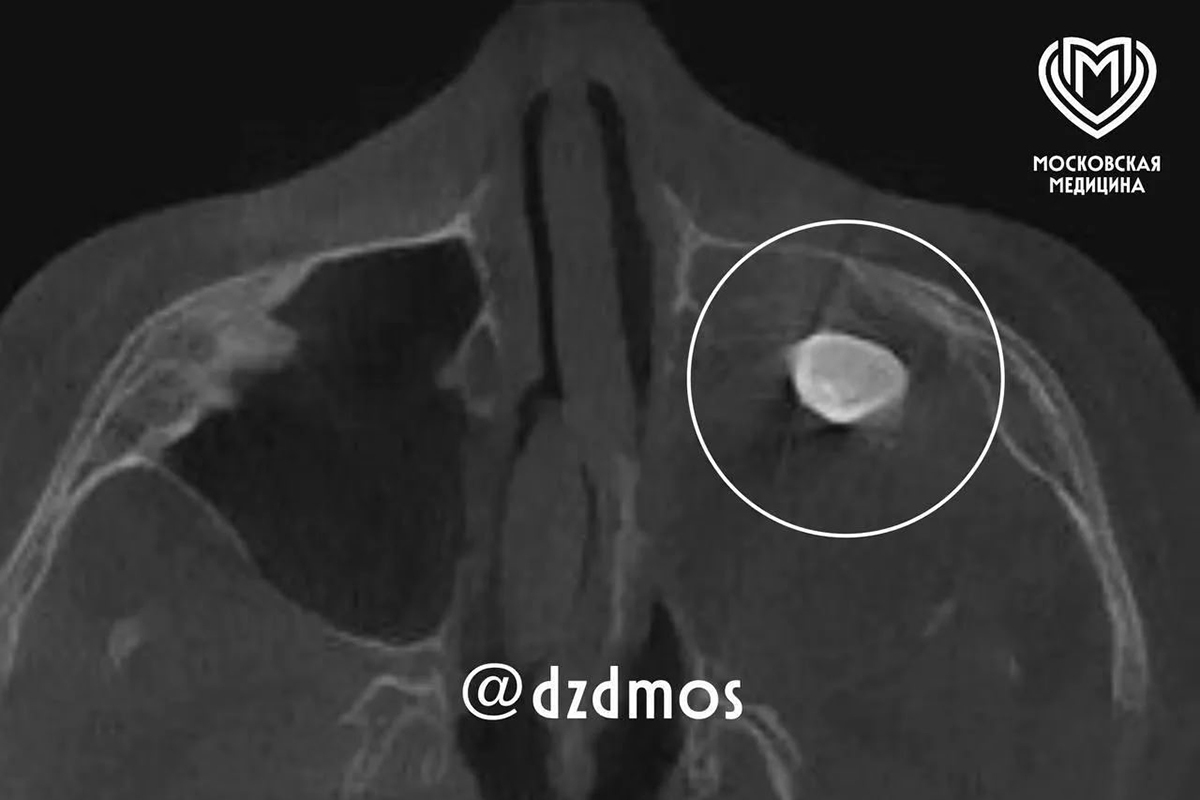

У 15-летнего москвича нашли зуб в носу

Выросший в носу у 15-летнего москвича зуб нашли врачи Филатовской больницы. Специалистам удалось успешно удалить его, сообщает столичный депздрав в своем канале в Max.